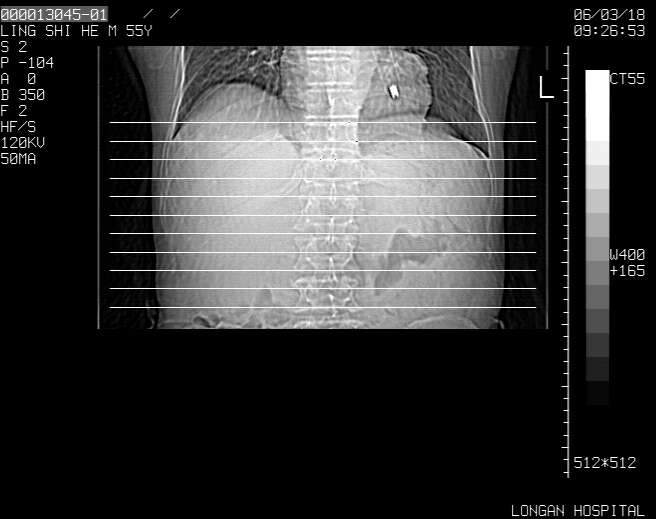

以下是引用guzhongliangddd在2006-3-21 22:13:00的发言:[br]病灶主要位于肝右叶的后份,内见异常血管,门脉主干及右支受侵{提示有癌栓形成},门腔间隙内见增大淋巴结。肝左叶内未见异常。

以下是引用zhuxinli在2006-3-22 1:23:00的发言:[br][br] 病灶主要位于肝右叶的后份,内见异常血管 .门脉右支截断,右叶前段早期强化(考虑动静脉漏),腹膜后肿大淋巴结,病灶逐渐强化,考虑为胆管细胞癌[br]